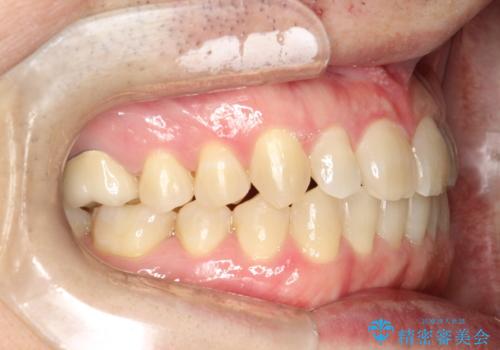

前歯の隙間 インビザラインにて整った歯並びへ

- 前歯の隙間が気になるとのことで来院されました。

インビザラインにて矯正治療を行うこととしました。

下の歯と歯の間にわずかに隙間をつくり、上の前歯の隙間を閉じました。